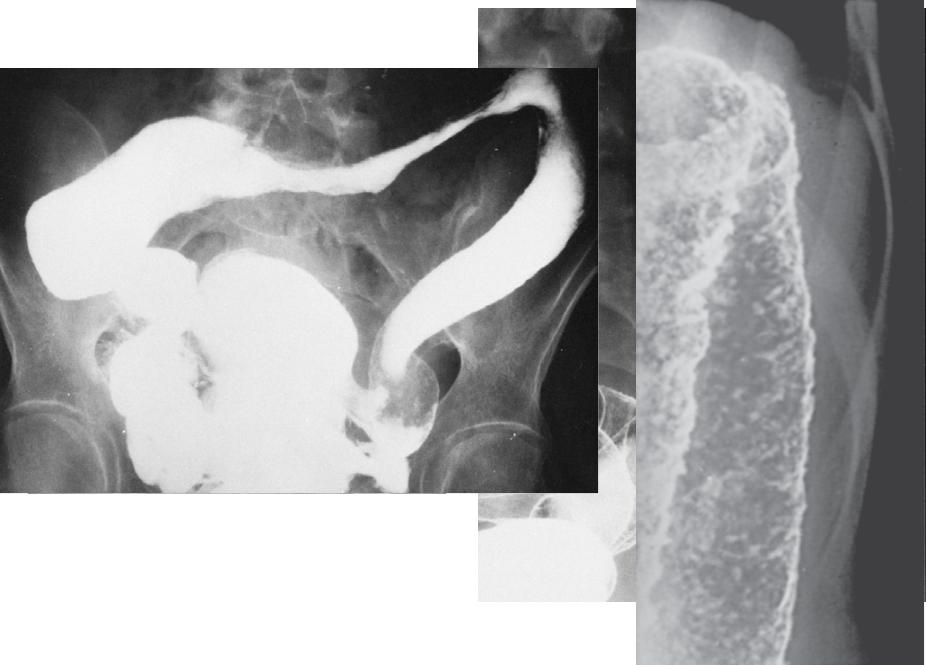

Язвенный колит: рентгенологические признаки